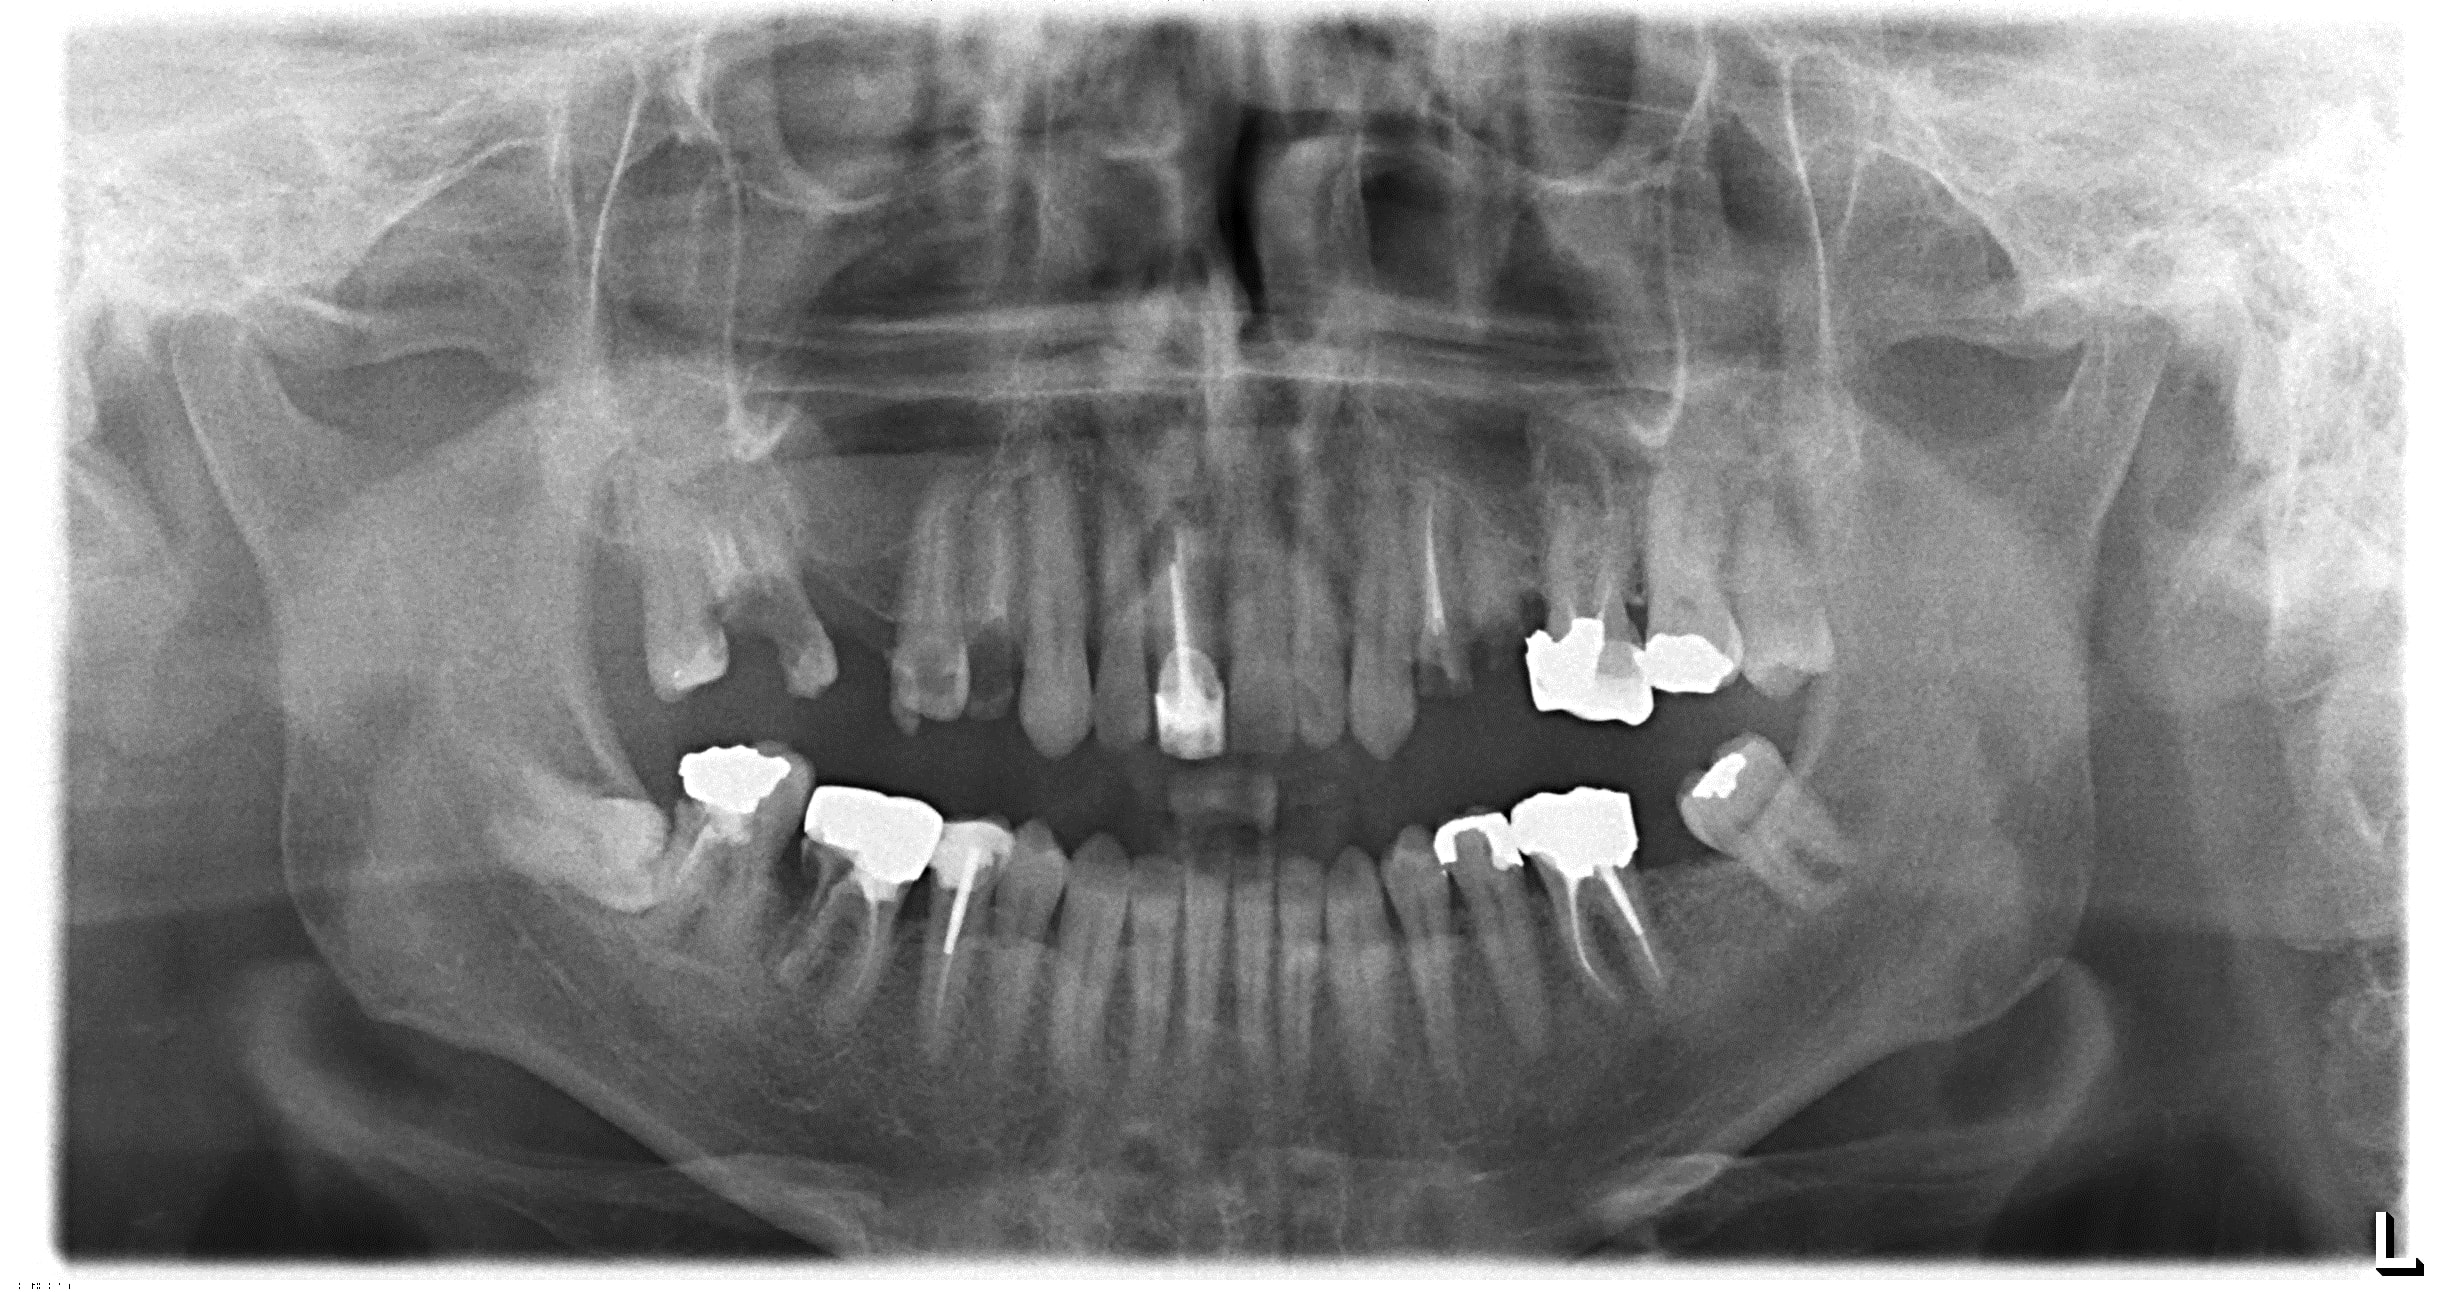

Je ne sais pas si tous tes clichés panoramiques sont du même acabit, mais je trouve que l'image manque singulièrement de précision... Beaucoup de bruit et pas net du tout!

On ne voit aucune ligne de manière nette, les dents ne sont pas bien individualisées, et paraissent comme ankylosées (on ne voit pas le desmodonte...). C'est pas nette du tout!

Une bonne pano doit te permettre de voir les différentes structures dentaires (émail, dentine, etc) et péridentaires (le desmondonte notamment), les caries, etc...

Cela ne m’étonne pas que tu puisses voir une obturation là où il n'y en a pas... Rien n'est bien délimité dans ta pano.

Pano : carie D de la 15 visible

Pano faite avec une OP200 D, que je vend si ça t'intéresse :-)))

Ta pano est magnifique Carident, très belle qualité. Petite critique ; la ligne sombre au dessus des apex est due au fait que la langue du patient n'est pas au palais. L'air laissé entre le palais et la langue donne cette zone sombre, qui gène la lecture du cliché.

Demande systématiquement au patient de "sucer" la tige sur laquelle il mord (choisi tes mots quand tu expliques cela !), cela aide à mettre la langue au palais même si pour certains c'est encore trop compliqué...